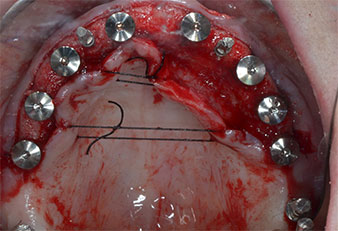

Tres años después, llegó el momento de colocar una prótesis del mismo tipo en el maxilar superior. Basándose en una planificación mediante tomografía computarizada de haz cónico (CBCT, por sus siglas en inglés), se evitó la necesidad de realizar una elevación del seno utilizando implantes cortos, mientras que una plantilla quirúrgica sirvió para transferir las posiciones planificadas al borde alveolar (figuras 1 y 2).

Para marcar las posiciones del implante y realizar la preparación piloto, se utilizó un inserto piezoeléctrico (Piezomed I1) con revestimiento de diamante y forma de llama (figura 3). Se tomaron precauciones para realizar movimientos hacia arriba y hacia abajo, con una potencia reducida, una irrigación completa y una baja presión (por debajo de 300 g). A continuación, se aplicó un inserto piloto (Piezomed I2A/I2P) para aumentar el diámetro inicial de 2 mm de los sitios de implante (figura 4), seguido de un inserto de 3 mm (Fig. 5).